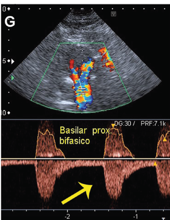

Inverted flow in the left vertebral artery!! And bidirection flow in the proximal basilar.